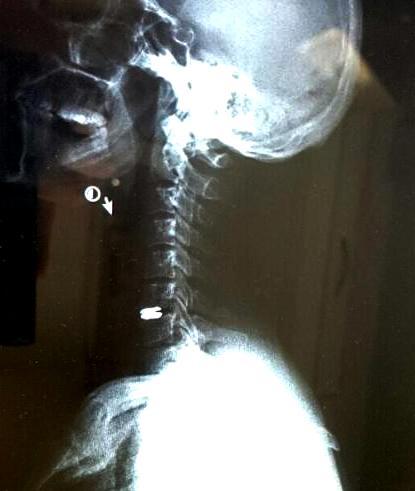

REBORN ANTERIOR CERVICAL SYSTEM

Anterior Cevical System, Cervical Cages and Plates Reborn® Anterior Cevical Fixation System is in t...